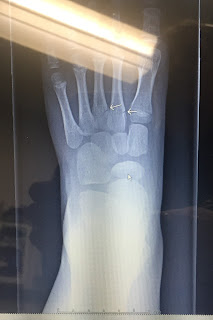

Then the broken foot. There would be no running or climbing at this birthday party. No laser tag, no ropes, no capture the flag, no Nerf gun war. Then I agreed to an Xbox party with less friends with 4 players total so no one would be left standing and watching. We agreed on 2 boys+Eli+Zeke on his actual birthday and I got suckered into 1 boy+Eli+Zeke+Daisy on Saturday.